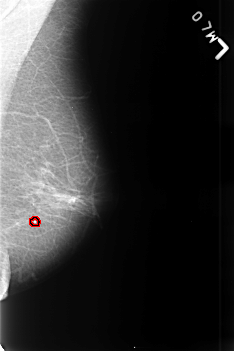

B_3447_1.LEFT_MLO

LEFT_MLO LINES 4552 PIXELS_PER_LINE 3040 BITS_PER_PIXEL 12 RESOLUTION 50 OVERLAY

FILE: B_3447_1.LEFT_MLO.OVERLAY

TOTAL_ABNORMALITIES 1

ABNORMALITY 1

LESION_TYPE CALCIFICATION TYPE ROUND_AND_REGULAR DISTRIBUTION N/A

ASSESSMENT 2

SUBTLETY 4

PATHOLOGY BENIGN_WITHOUT_CALLBACK

TOTAL_OUTLINES 1

BOUNDARY